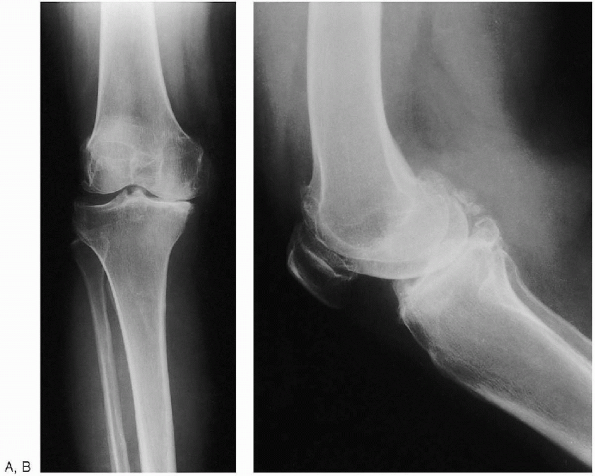

FIGURE 28-2. Anteroposterior standing (weight bearing) (A) and lateral (B) preoperative radiographs of the knee.

and a sunrise view of the affected knee are obtained. A long, standing,

anteroposterior radiograph showing the center of the femoral head, the

knee, and as much of the tibia as possible (preferably including the

ankle) can also be obtained. This type of radiograph is especially

useful in patients with suspected abnormal femoral or tibial geometry,

in which the mechanical axis may be difficult to determine. If long

x-ray films are not available, an anteroposterior radiograph (14

17 inch x-ray film) of the entire femur permits similar calculations. Todetermine the angle between the mechanical and anatomic axes, the

surgeon draws two lines to the center of the distal femur at the knee:

one from the center of the femoral head and the second from the center

of the femoral shaft, simulating the position of the intramedullary

alignment rod that will be used during surgery. The resultant

angle is usually 5 to 7 degrees. It may be less than 5 degrees in